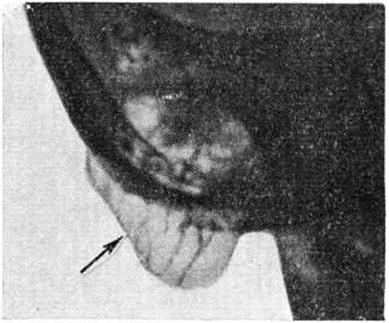

Крупная одиночная ячейка в сосцевидном отростке (относительно редкий анатомический вариант), дающая в норме на рентгенограмме интенсивное просветление, может быть принята за Мастоидит с субпериостальным абсцессом (рисунок 4). Отличить полость субпериостального абсцесса от полости, вызванной холестеатомой в сосцевидном отростке, можно по характеру их границ. Полость субпериостального абсцесса, как правило, не имеет чётких очертаний, свойственных холестеатоме (смотри полный свод знаний). В сомнительных случаях диагностика проводится только путём клинико-рентгенологическое сопоставлений. Верхушечный Мастоидит (абсцесс Бецольда) может быть легко пропущен, если сделать одну боковую рентгенограмму височной кости (рисунок 5, а). При толстой наружной пластинке коркового вещества сосцевидного отростка костный дефект внутренней пластинки на боковом снимке не обнаруживается. На снимке в косой проекции по Стенверсу дефект этой пластинки выявляется чётко (рисунок 5, б). Для распознавания верхушечного Мастоидит очень важен учёт клинические, симптомов, определяющих тактику рентгенолога. Симптом полости рентгенологически нередко обнаруживается и при замаскированных Мастоидит при лечении антибиотиками. Рентгенологические наблюдение показывает, что консервативное лечение Мастоидит при благоприятных исходах ведёт к полной костной регенерации полости абсцесса и восстановлению воздушности сохранившихся ячеек. Серийное послойное рентгенологическое исследование височной кости таких больных указывает на замещение дефекта нормальной костной тканью (рисунок 6, а, б) и перестройку сосцевидного отростка, тип строения которого из распространённого пневматического становится смешанным спонгиозно-пневматическим. Рентгенологические наблюдения указывают на длительность этого процесса (1 — 2 года).